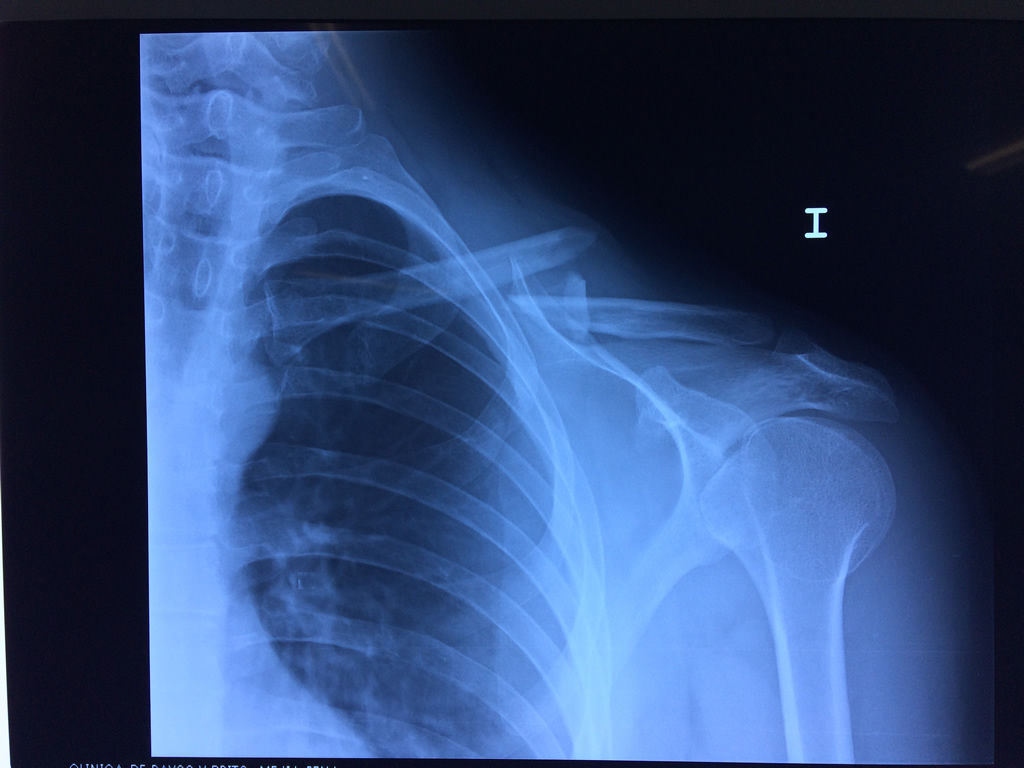

Cirugías de Hombros - Clavícula

La clavícula es un hueso largo, con forma de "S" itálica, situado en la parte anterosuperior del tórax. Junto con la escápula forman la cintura escapular. Se puede palpar por toda su longitud y se extiende del esternón al acromion de la escápula, siguiendo una dirección oblicua lateral y posterior.

Se considera el único medio de unión entre el miembro superior y el tórax. A pesar de su aspecto, similar al de un hueso largo, posee una estructura semejante a la de un hueso plano, ya que carece de epífisis y de diáfisis, lo que la harían entrar dentro de la clasificación de hueso largo. Carece de un canal medular propiamente dicho.